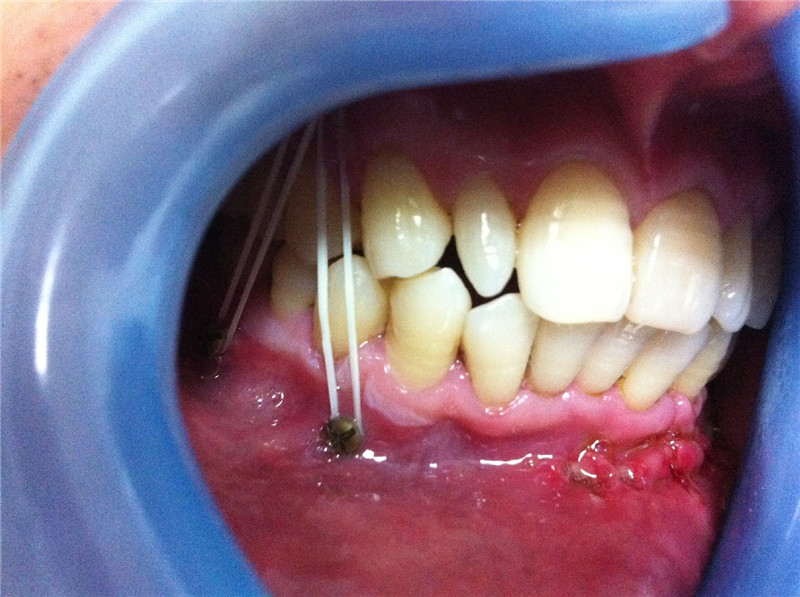

頜面部骨折導(dǎo)致的面容及咬合關(guān)系的改變

堅(jiān)強(qiáng)內(nèi)固定聯(lián)合變化的頜間牽引保證術(shù)中以及術(shù)后咬頜關(guān)系的恢復(fù)